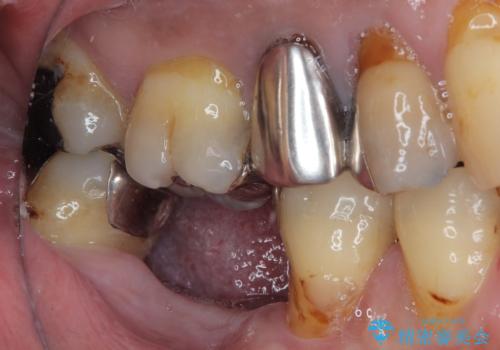

- 奥歯を抜歯してから放置しているとのことで来院された患者様です。

歯が割れて抜歯になってしまったとのことで、咬合力に抵抗できるよう、インプラントによる補綴治療を行うこととしました。

むし歯の放置期間と抜歯してからの放置期間が長く、咬み合わせる上顎の歯がやや伸び出している状態でした。

上顎の部分矯正や対合歯の補綴治療も提案しましたが、今回は欠損部のみの治療を行いました。